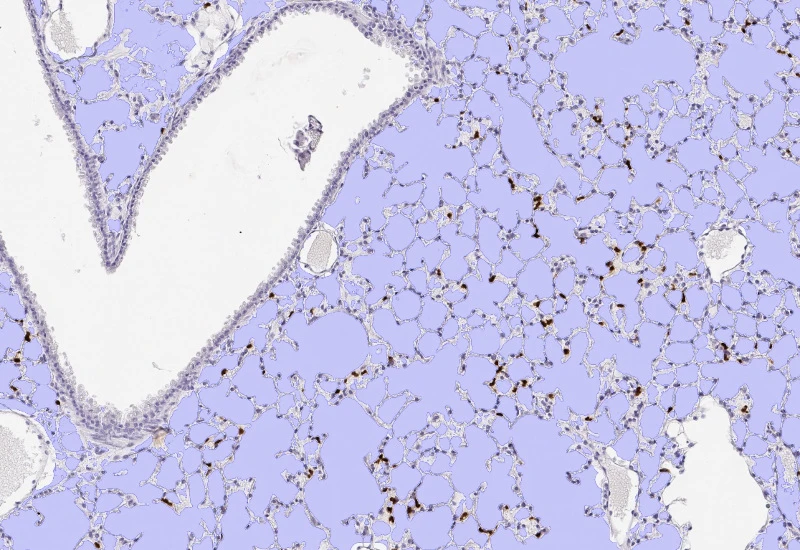

Segment nuclei and lung metastructures (total tissue, bronchioles, vessels, alveoli), detect cellular phenotypes within each component, and measure up to 20 morphometric parameters per metastructure and nucleus.

The Pulmo App segments nuclei as well as the metastructure components of lung, including total tissue, bronchioles, blood vessels and alveoles. Further it detects cellular phenotypes within the metastructure components. Each segmented metastructure/nuclei is measured for up to 20 morphometric parameters.